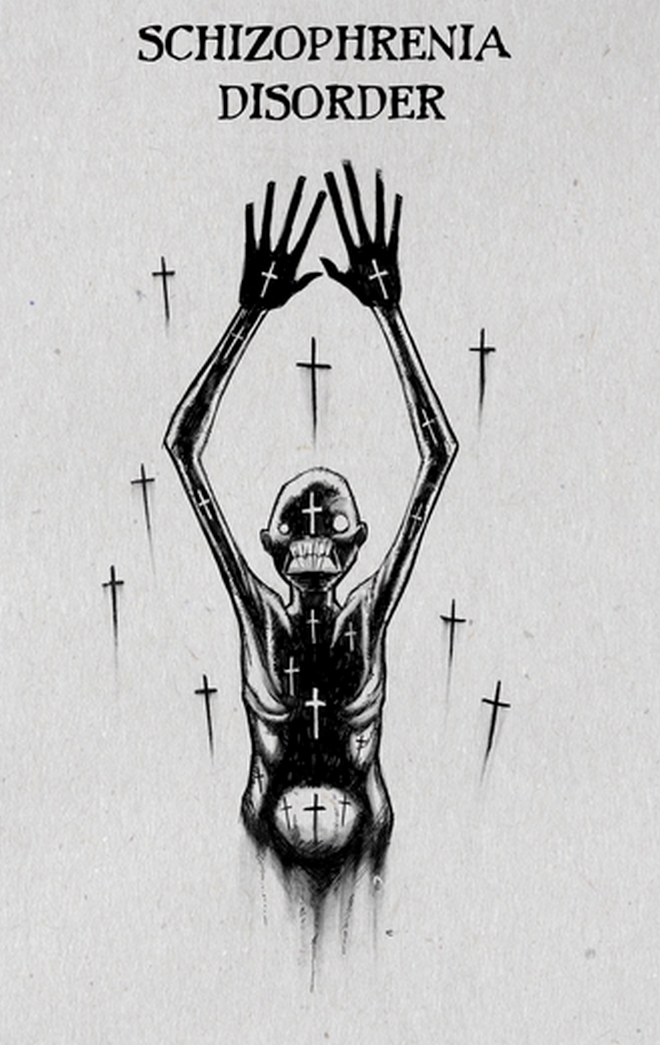

Σχιζοφρένεια